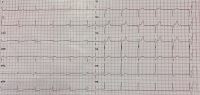

EKG - Notaufnahme

Abbildung 1: EKG bei Vorstellung in der Notaufnahme. Es zeigen sich eine geringe ST-Streckenhebung in der Ableitung aVL sowie reziproke ST-Streckensenkungen in den Ableitungen II und III. Da die Ableitung III im Cabrerakreis in Richtung –60 ° zeigt, verhalten sich die Ableitungen aVL und III eindeutig reziprok zueinander, weswegen die Kombination der ST-Streckensenkungen in III gemeinsam mit der ST-Streckenhebung in aVL quasi einem STEMI-Äquivalent in zwei benachbarten Ableitungen des Cabrerakreises entspricht.